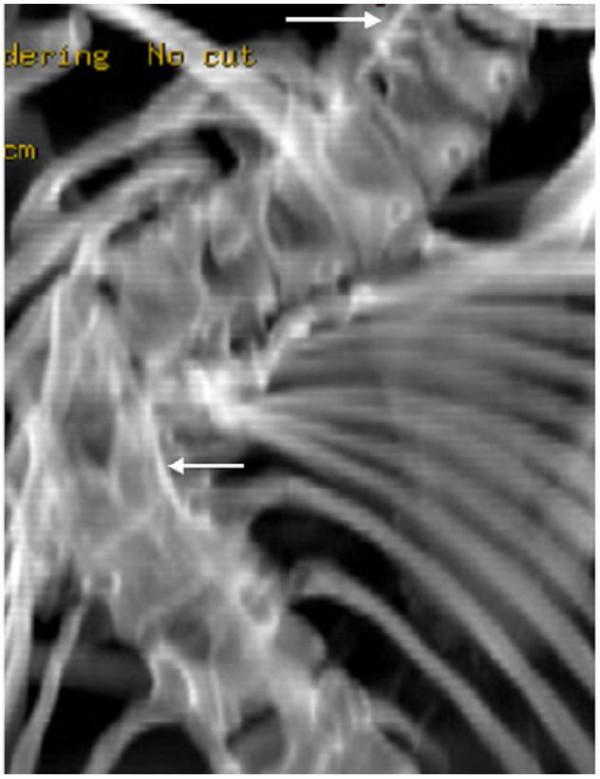

Atlanto-axial rotatory fixation in a girl with Spondylocarpotarsal synostosis syndrome.

We report a 15-year-old girl who presented with spinal malsegmentation, associated with other skeletal anomalies. The spinal malsegmentation was subsequently discovered to be part of the spondylocarpotarsal synostosis syndrome. In addition, a distinctive craniocervical malformation was identified, which included atlanto-axial rotatory fixation. The clinical and the radiographic findings are described, and we emphasise the importance of computerised tomography to characterize the craniocervical malformation complex. To the best of our knowledge, this is the first clinical report of a child with spondylocarpotarsal synostosis associated with atlanto-axial rotatory fixation.